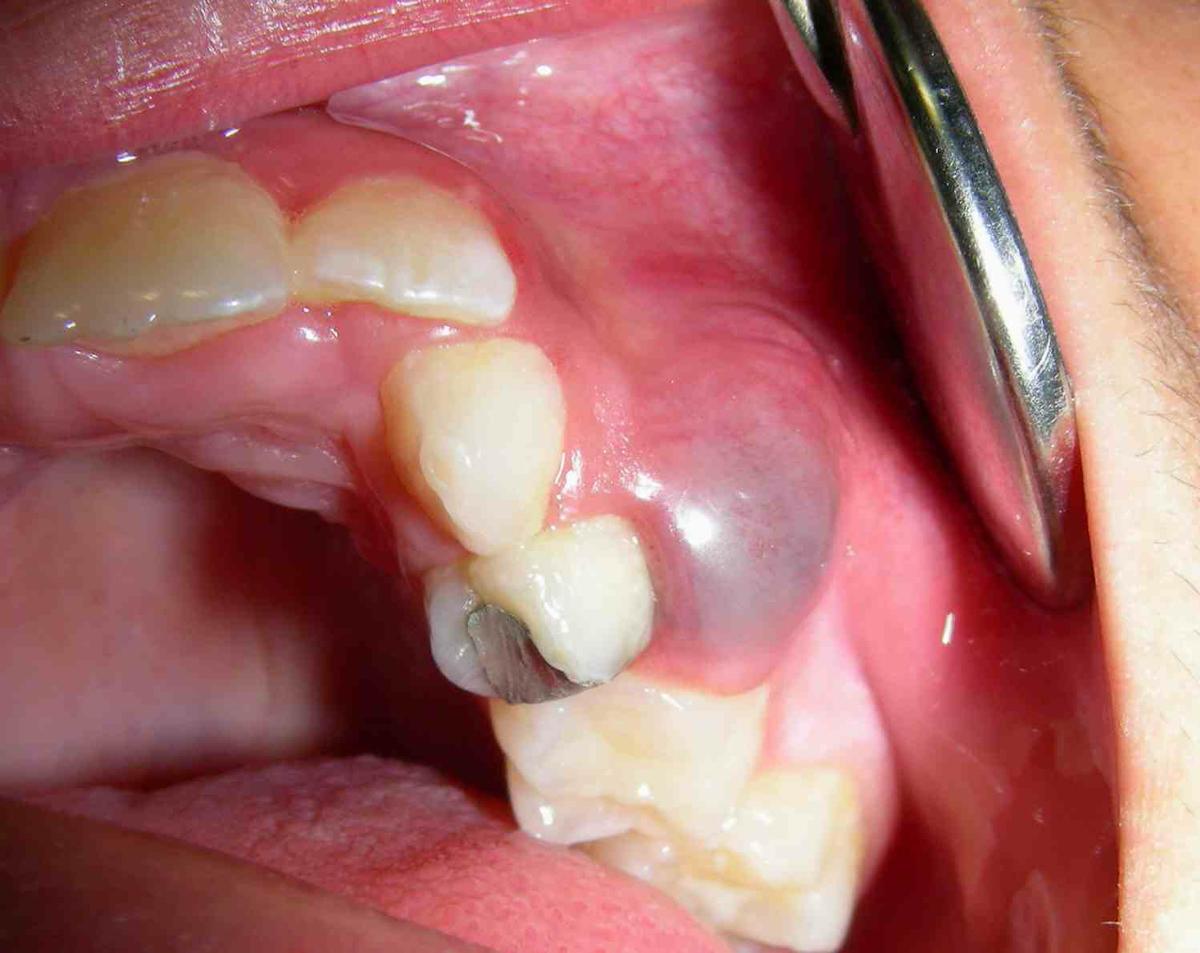

Paciente masculino de 12 años de edad que presenta quiste dental observado clínicamente en la unidad dentaria 24

6) Quiste periapical:

Cavidad patológica que se encuentra rodeada de epitelio, la cual puede mantener material semisólido en su interior, y restos de celular. Son quistes odontogenicos que derivan de los restos epiteliales de Malassez, llamados quistes inflamatorios porque derivan de un granuloma apical preexistente.